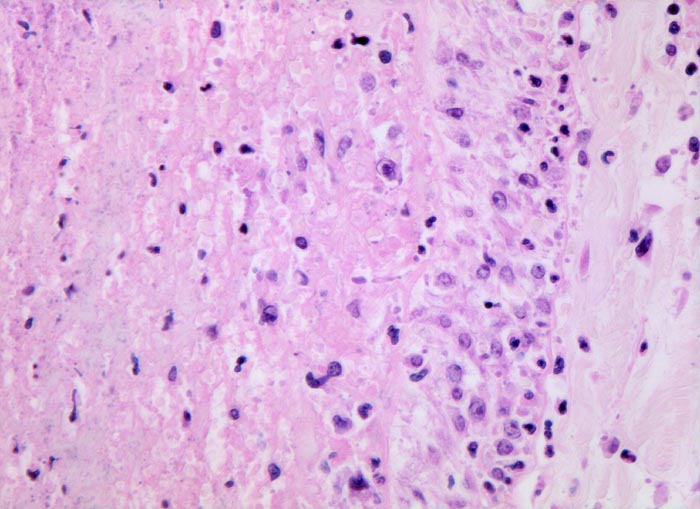

frische Lungenembolie

Rechts im Bild die Gefässwand. Links im Bild der Embolus bestehend aus Fibrin und zerfallenden neutrophilen Granulozyten. An der Grenze zwischen Gefässwand und Embolus hat sich noch kein Organisationsgewebe ausgebildet. Man sieht an dieser Stelle jedoch zahlreiche eingewanderte Monozyten.

Tiefe Beinvenenthrombosen bei metastasierendem Prostatakarzinom. Koronare Herzkrankheit.